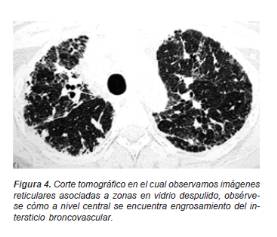

En cambio los casos crónicos presentan un patrón nodular sumado a opacidades reticulares finas y gruesas (patrón reticulonodular) de predominio central con engrosamiento del intersticio broncovascular, que en forma paulatina progresan a una imagen de conglomerados fibróticos o áreas quísticas o en «panal de abeja» (Figura 4).